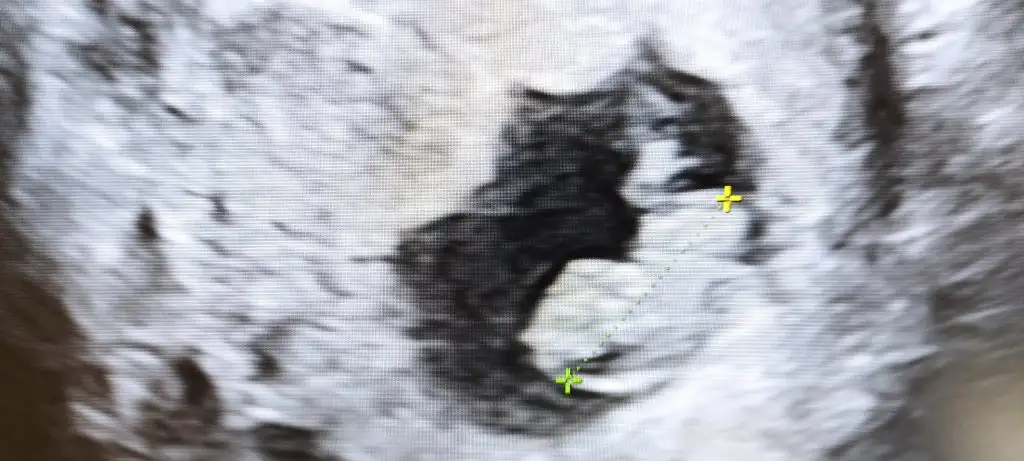

Geçen birkaç video izlemiştim. Genital kısımda 3 tane ince beyaz çizgi olunca kız diye anlatıyordu doktor. Bayağı örnek görmüştüm. Siiznki de öyle duruyor ama tabiki. Bu sadece bir tahmin allah gönlünğzden geçeni nasip etsin inşallahnerden anladınız acaba :)

Bana da baksanızGeçen birkaç video izlemiştim. Genital kısımda 3 tane ince beyaz çizgi olunca kız diye anlatıyordu doktor. Bayağı örnek görmüştüm. Siiznki de öyle duruyor ama tabiki. Bu sadece bir tahmin allah gönlünğzden geçeni nasip etsin inşallah